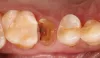

Фото 1: Зуб 2.5 перед удалением.